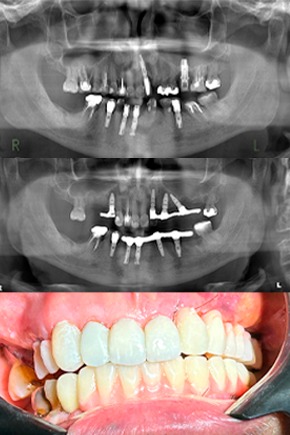

Protocolo em maxila atrófica sem enxerto. Usando o osso residual do pilar canino.

Protocolo em maxila e mandíbula atrófica sem enxerto.